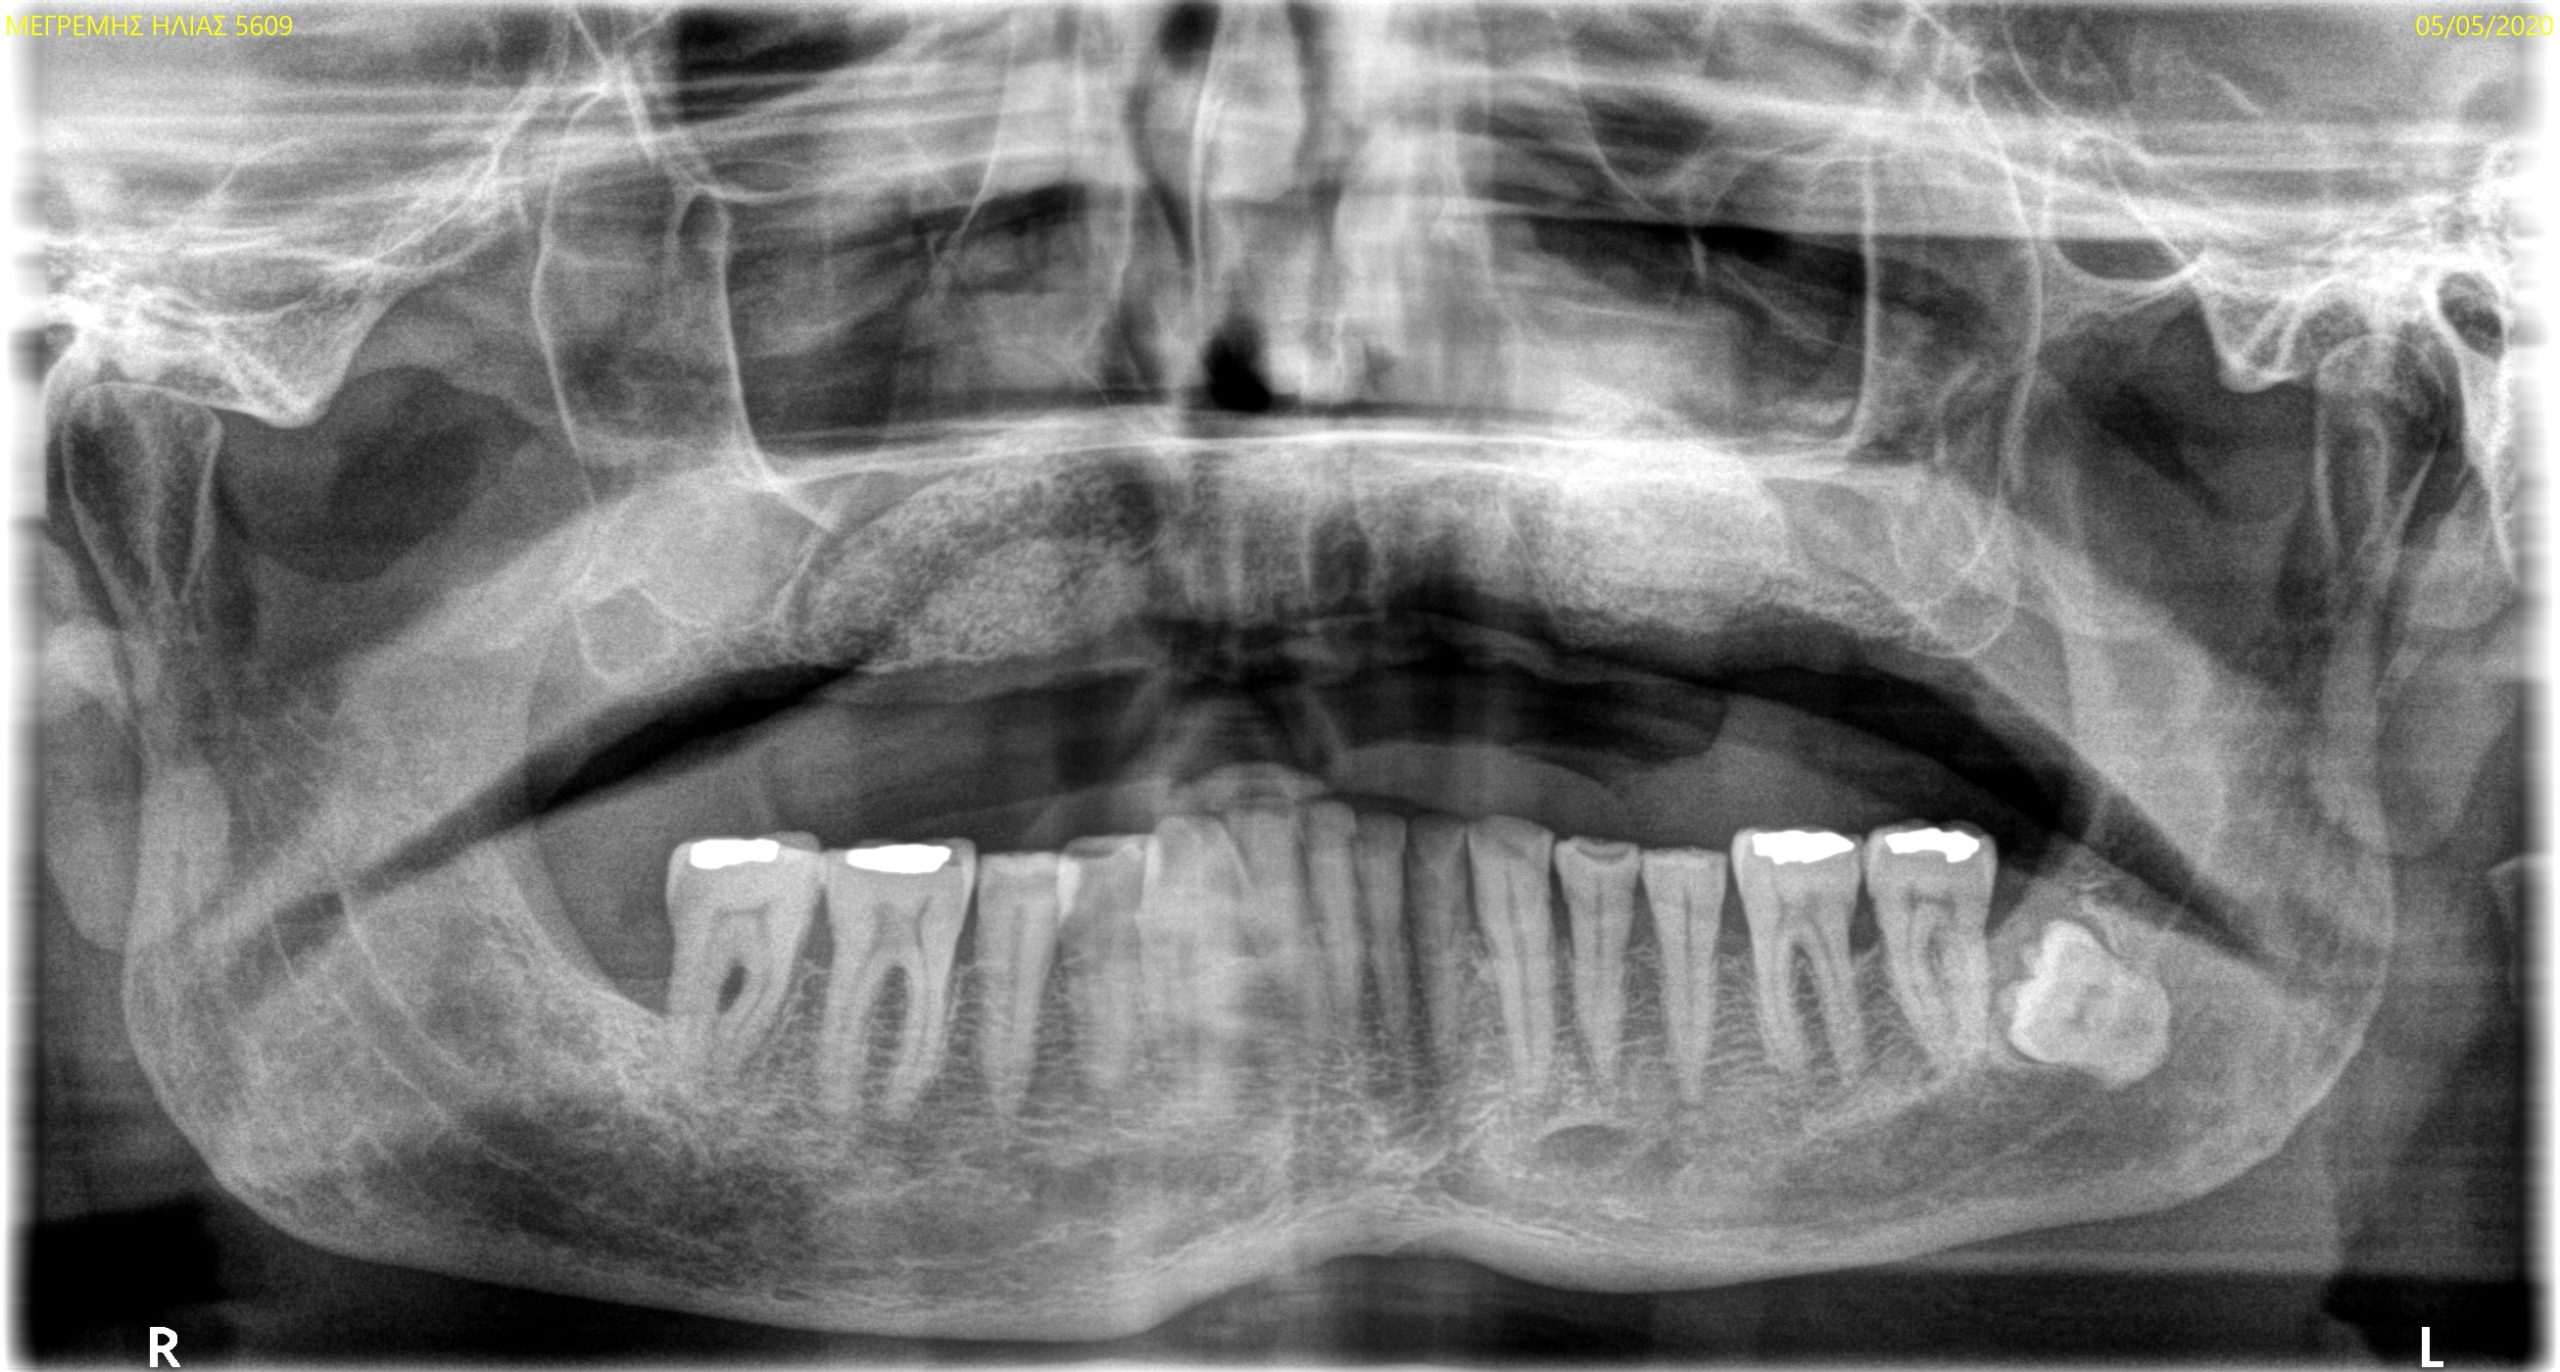

Total upper and lower rehabilitation using CDP technology as an analysis and planning tool

Case study carried out with Athena Smile Pelekanos (GR ) : dott . Stavros Pelekanos

The use of CDP (Complete Digital Patient) as a basis for planning in a case of complete implant rehabilitation with a full arch in zirconia – ceramicised

Complete Digital Patient (CDP): guided surgery for complete upper and lower rehabilitation with zirconia-ceramic screw-retained implants

Complete Digital Patient (CDP): the use of guided surgery for implant restoration in total upper and lower rehabilitation with titanium bars and different types of zirconia-ceramic